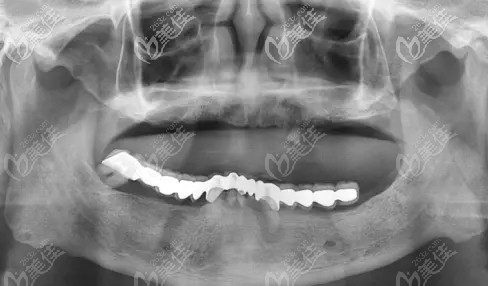

我牙齒一直不好,前段時(shí)間去醫(yī)院檢查,醫(yī)生說(shuō)我的牙齒已經(jīng)三度松動(dòng)了,建議還是做全口種植牙,但是我還是猶豫了,因?yàn)樽约旱难例X還沒(méi)有脫落不想拔牙。不過(guò)這段時(shí)間發(fā)現(xiàn)牙齒已經(jīng)基本不能咬東西了,思來(lái)想去還是得做種植牙,然后就在網(wǎng)看好多人說(shuō)韓國(guó)登騰allon4全口種植牙效果不錯(cuò),性價(jià)比也高,不知道5萬(wàn)元能不能做?